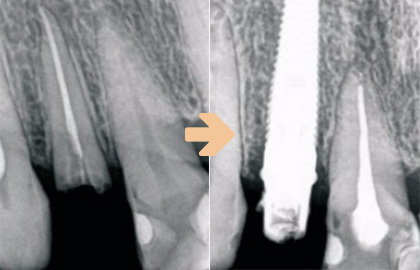

발치 즉시 임플란트

치료기간 단축을 위한 임플란트 시술

발치당일 임플란트를 식립하고 고정성 임시 보철물을 당일 시술하는 방법으로 치아가 완성되기 전까지 상당기간 기다려야 하는 불편함을 없앨 수 있는 시술법